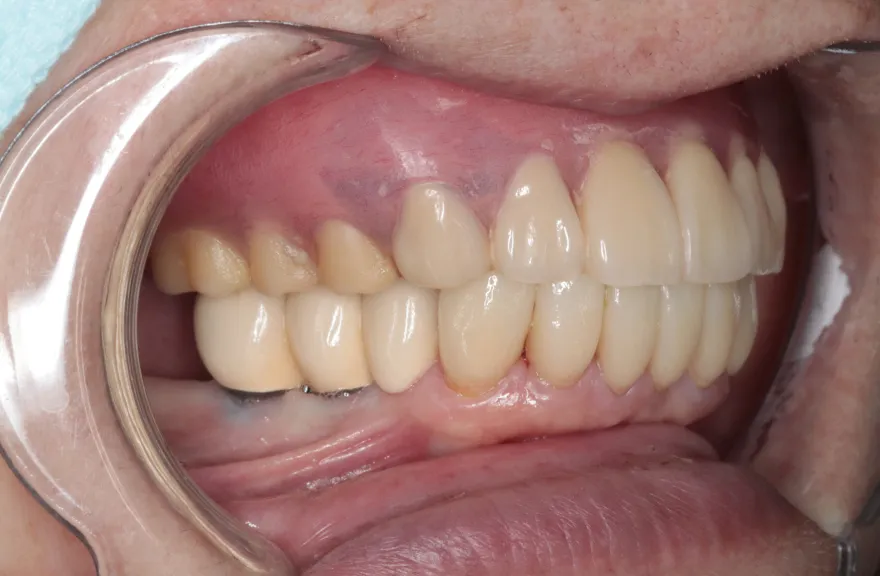

写真の通りに治療を終了いたしました。

上顎は総義歯の形態に、下顎は十分な寿命を持った歯は残して、長期的な保存が難しい歯はインプラント治療を施しました。上顎を総義歯形態にすることにより、何かが起こっても義歯の修理を行えば対応が可能です。即日の修理・完了も難しくないでしょう。

下顎は十分な寿命を持った歯しか残していないので、今後の人生でよっぽどのことがない限りトラブルが起きないと考えます。インプラント治療を施してある部分も、同様にトラブルが起きにくいと考えています。歯周病になった、とか歯が欠けた、というインプラント治療の悪い面が聞こえてくるようになりましたが、噛み合う上の歯を総義歯とすることで、過大な力がかかることなく、トラブルが起きにくい結果を得ることができました。

上顎は総義歯ですが、『今まで食べられなかったものがなんでも噛めるようになった』と、患者さんよりお言葉を頂戴しております。